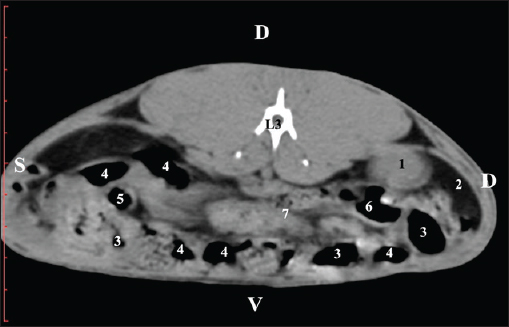

At the L3 level, the anatomical adjacencies of the right kidney with the pars descendens of the duodenum, ileum, cecum, and colon descendens were visualized. Hypoattenuated right ureter and normoattenuated gl. adrenalis dextra were situated medially to the right kidney. Extremitas caudalis of the right kidney was a clearly visible normoattenuated finding, surrounded by hypoattenuated borders of abdominal adipose collections (Figs. 6 and 7).

Fig. 6. Pre-contrast CT anatomical scan of the regio-abdominis media at the cranial L3 edge level. (1) Ren dexter; (2) lobus caudatus (proc. caudatus) with visceral adipose tissue; (3) gl. adrenalis dextra; (4) pars descendens of the duodenum; (5) ileum; (6) cecum; (7) colon ascendens; (8) jejunum; (9) lien; (10) colon ascendens; (11) colon transversum; (12) colon descendens, (*) mesenterium.

Fig. 7. Pre-contrast computed tomography (CT) anatomical scan of the regio-abdominis media at the caudal L3 edge level. (1) Ren dexter; (2) adipose collection; (3) cecum; (4) colon ascendens; (5) colon transversum; (6) colon descendens; (7) mesenterium.